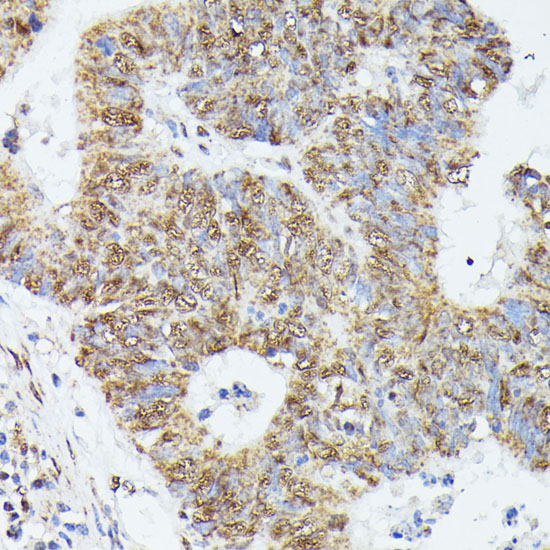

Immunohistochemistry of paraffin-embedded human colon using KIF22 at dilution of 1:100 (40x lens).

Immunohistochemistry of paraffin-embedded human colon carcinoma using KIF22 at dilution of 1:100 (40x lens).

Immunohistochemistry of paraffin-embedded human breast cancer using KIF22 at dilution of 1:100 (40x lens).

应用详情:WB 1:200 - 1:2000

IHC 1:50 - 1:200

IF 1:50 - 1:200